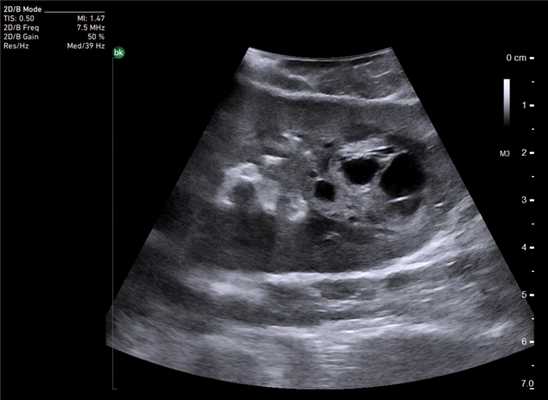

У 5 (41,7%) из 12 пациенток образования в печени имели гиперэхогенную, гомогенную структуру с четкими и ровными контурами размером от 5 до 12 мм в диаметре, которые были интерпретированы как доброкачественные образования печени — гемангиомы (табл. 2). У 4 (33,3%) пациенток образования имели анэхогенную гомогенную структуру, с четкими и ровными контурами, с гладкой внутренней выстилкой и эффектом усиления эхосигнала, размером от 3 до 11 мм в диаметре, и были интерпретированы как кисты. В 3 (25%) случаях в печени были выявлены гипоэхогенные образования солидной гетерогенной структуры с нечеткими, но ровными контурами размером от 10 мм в диаметре (рис. 1) до 22×17×15 мм в одном случае, расположенное на диафрагмальной поверхности печени, которое «самоампутировалось» в процессе исследования и при срочном гистологическом исследовании оказалось метастазом аденогенного рака (рис. 2).

Рис. 2. Метастаз аденогенного рака.

Особенностью проведения интраоперационного ультразвукового исследования у пациентов с первичным поражением печени является то, что гепатоцеллюлярный рак часто развивается на фоне цирроза печени. Следовательно, если опухоль локализуется в толще паренхимы, а так же имеет не большие размеры, пальпаторно определить ее границы крайне затруднительно. Таким образом, задачи установленные перед интраоперационной ультразвуковой томографией были несколько иными, а именно: определение границ опухоли, разметка зоны резекции, определение связи с магистральными сосудами (рис. 2 а,б).

Рис. 2. Метастатические очаги (стрелки) в печени на фоне цирроза.